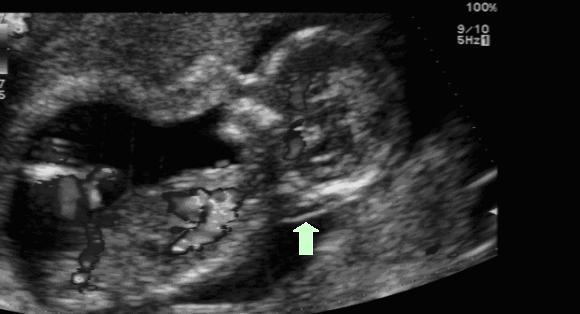

孕期超声检查之NT

一旦确认了怀孕,许多准妈妈们就开始了一趟担忧之旅:宝宝发育的情况如何?他是否健康?会不会有先天畸形?幸好技术的进步让我们有各种手段来提前知晓和预防...